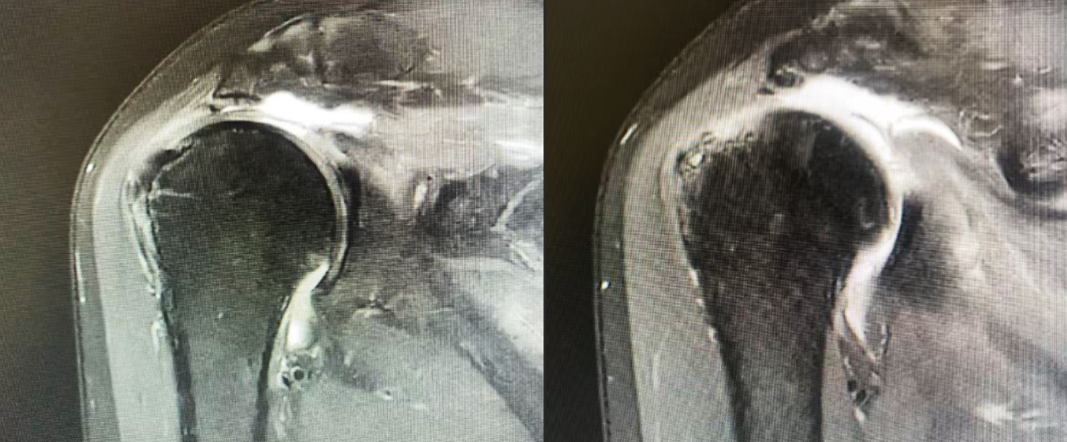

MRI显示肩袖巨大撕裂,肌腱断端回缩至关节盂水平

还好找到深圳二院龙华医院运动医学科钟名金博士!钟名金博士结合患者年龄、需求及影像学评估,认为虽然肩袖撕裂大,肌腱回缩远,但好在新鲜受伤,肌腱质量较好,肌腱脂肪化不严重(Goutalliar I-11级),不用大动干戈,完全可以进行“关节镜下肩袖修补术”。丽阿姨认真听取钟博士对病情的细致讲解以及了解既往多个类似成功案例,毅然决定来到深圳二院龙华医院住院手术治疗。